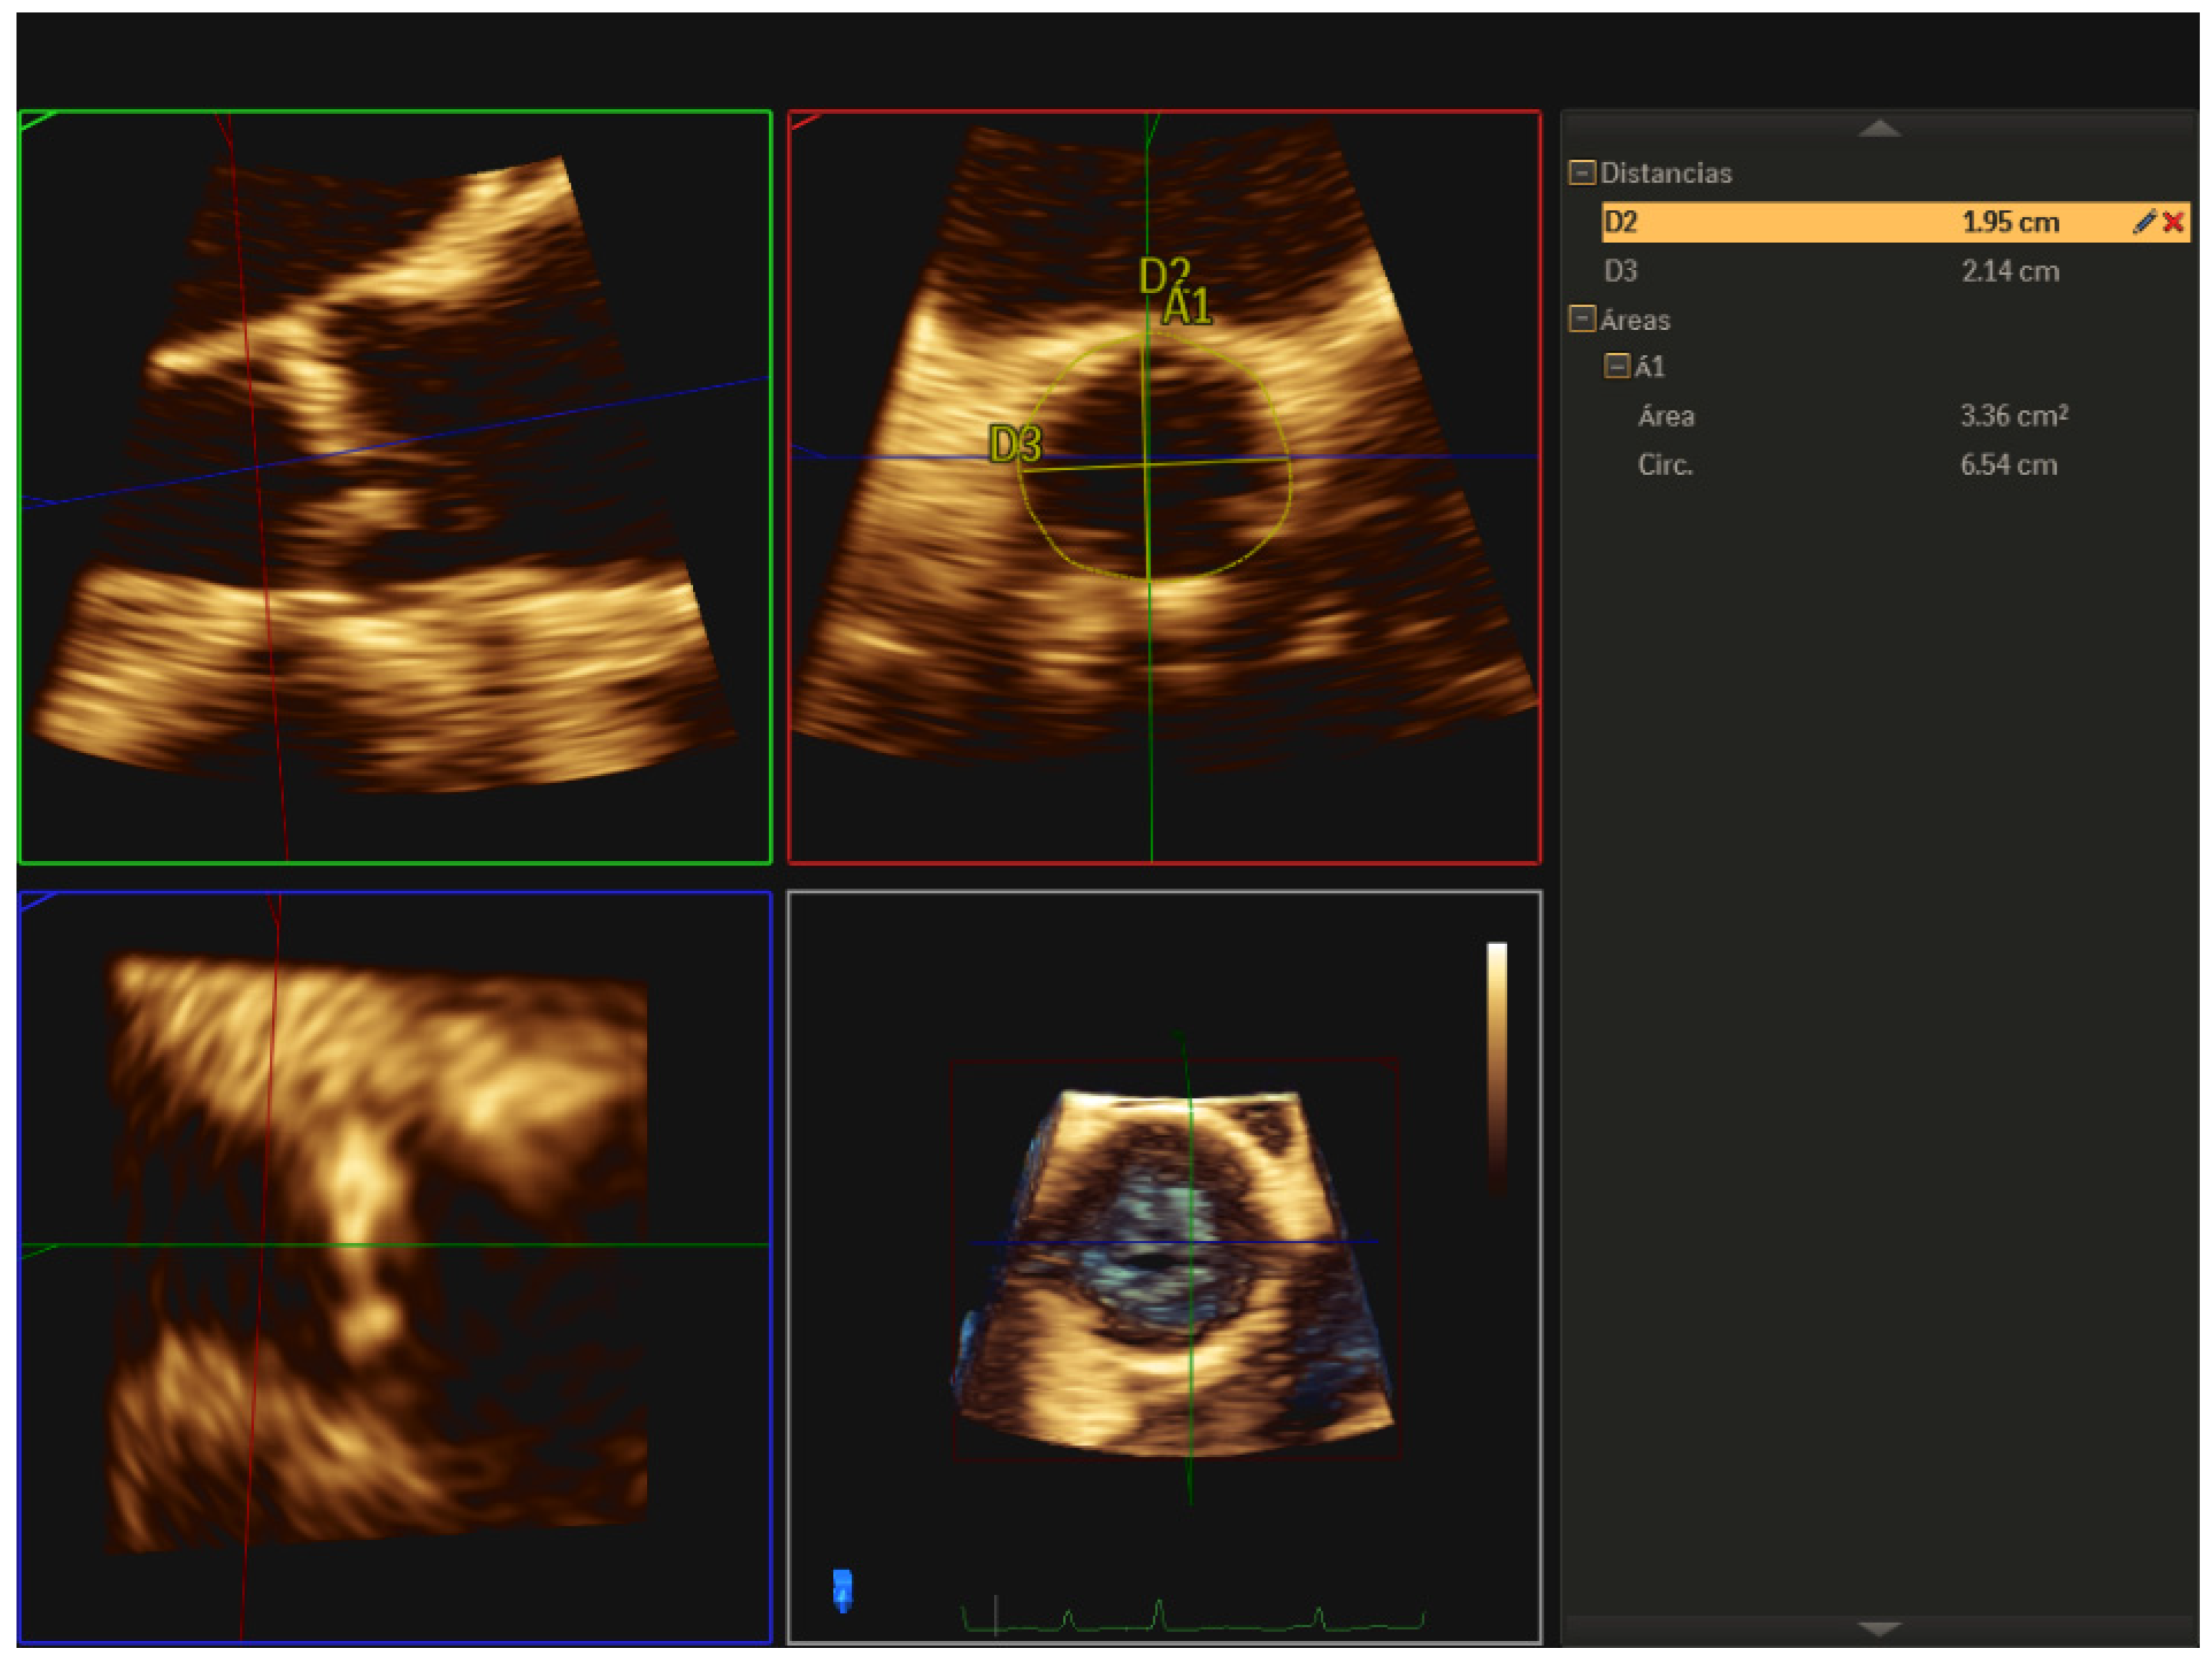

At present, it is recommended to measure the aortic annulus with a 3D imaging technique (multidetector computed tomography, 3D-TEE, or cardiac magnetic resonance) since the measurement obtained with a two-dimensional echocardiogram tends to systematically underestimate the size of the annulus [3]. In a series of 256 patients undergoing TAVR, annulus assessment by 3D-TEE modified the choice of prosthesis size in 23% of patients compared to if it had been based solely on 2D-TEE [4]. Similarly, measurement of the aortic annulus using 3D-TEE has been shown to reduce the incidence of perivalvular aortic regurgitation after TAVR compared to measurement with 2D-TEE [4]. For the correct measurement of the annulus using 3D-TEE, we acquire the valve in Zoom mode, and we measure the annulus in systole between the hinge points located at the junction of the leaflets with the LVOT using the multiplanar reformatting mode (MPR) (Figure 5). The 3D study of the aortic annulus makes it possible to obtain multiple measurements that include the largest and smallest diameters, the perimeter and the area, as well as the calculation of the diameters derived from the perimeter and the area. These parameters allow us to refer to the manufacturers’ tables to choose the most appropriate prosthesis size for each case. The dimensions of the annulus change throughout the cardiac cycle, so it is recommended that the acquisition of the images be carried out synchronously with the electrocardiogram and the measurements be made in systole, in the 30–40% of the RR interval, since this is the moment in the cardiac cycle during which the annulus reaches its maximum dimensions. Kasel et al. [5] proposed a novel method called the “turnaround rule” as a technique to improve annular measurements using 3D-TEE. First, the transverse and sagittal and coronal orthogonal planes are oriented along the aortic root, such that all planes intersect at the center of the opened valve, with the sagittal and coronal planes aligned parallel to the long axis of the ascending aorta. Second, the orthogonal planes are rotated to identify the most caudal attachments of the aortic valve leaflets (hinge points). The transverse plane is repositioned from the aorta toward the ventricle until it reaches the level of the hinge points. Finally, the orthogonal planes are repeatedly rotated (the turnaround rule) to ensure that the hinge points of the aortic valve leaflets are transected by the transverse plane. The annulus minimal and maximal dimeters as well as the perimeter and annular area, can then be measured on the transverse plane.

Figure 5.

Measurement of the aortic valve annulus by 3D-TEE using the multiplanar reformatting (MPR) mode, obtaining major, minor diameters, area, and perimeter.